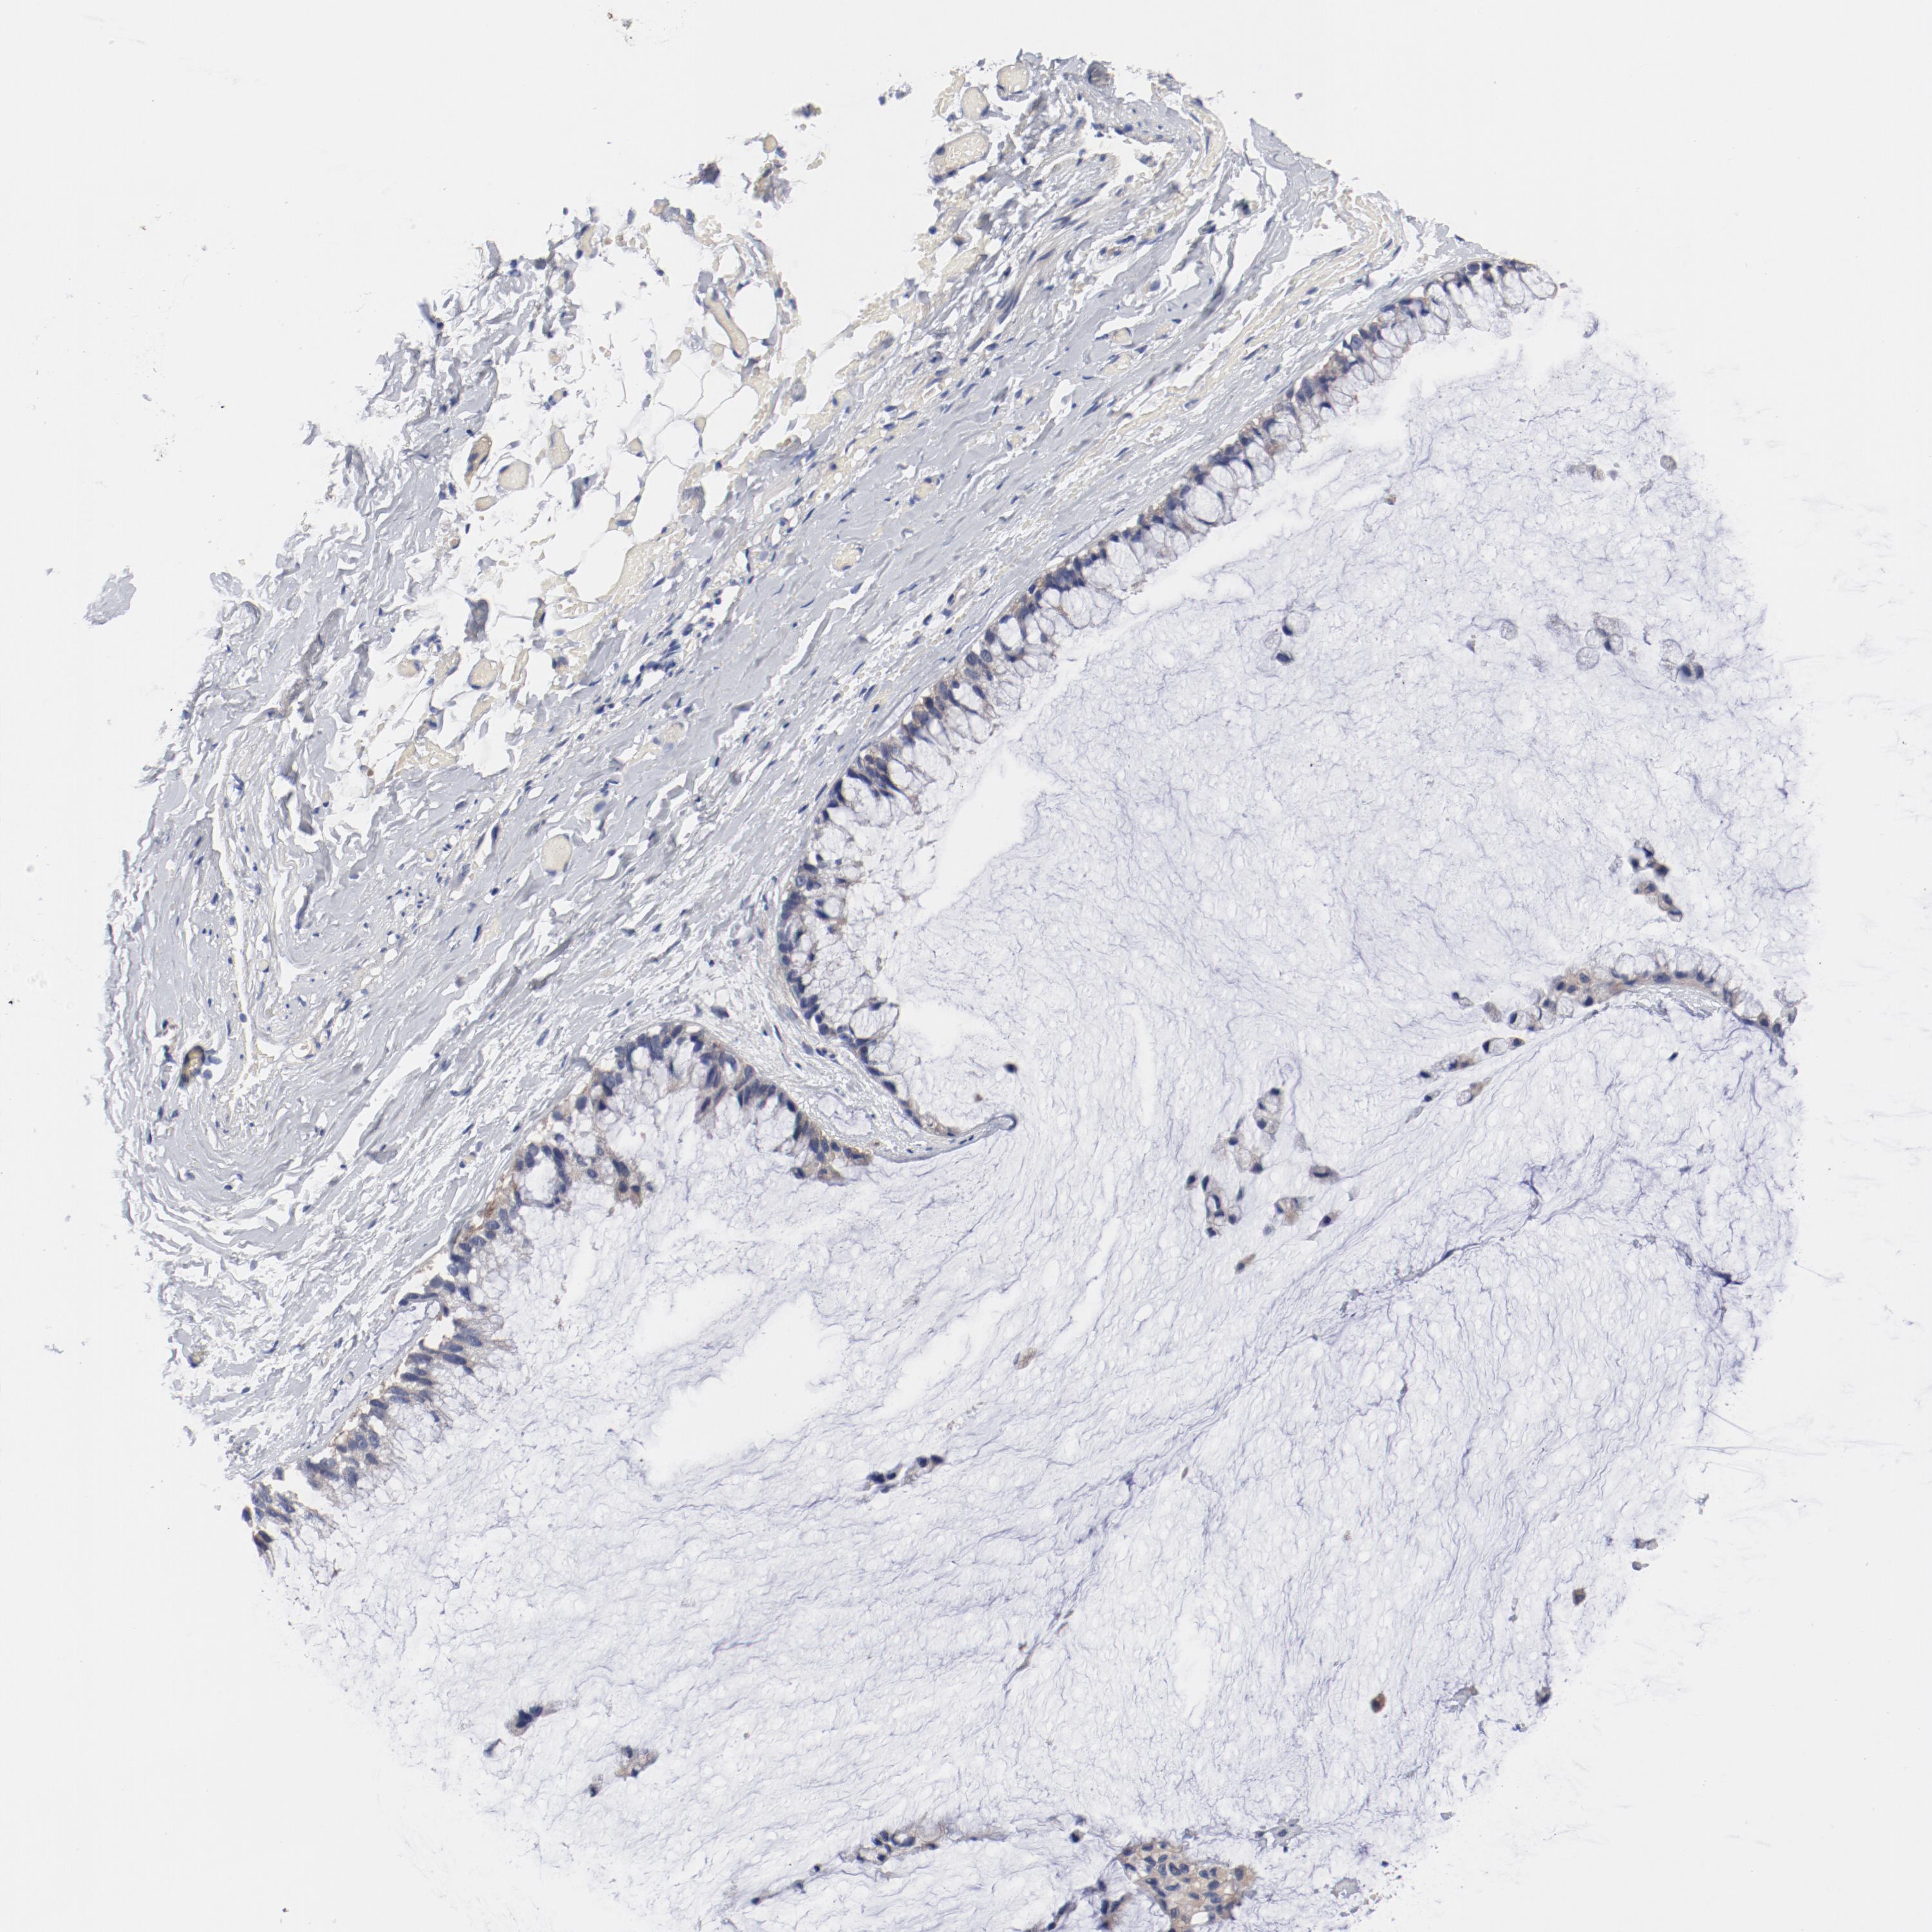

OVARIAN CANCER - Protein expressioni

A mouse-over function shows sample information and annotation data. Click on an image to view it in a full screen mode. Samples can be filtered based on level of antibody staining by selecting one or several of the following categories: high, medium, low and not detected. The assay and annotation is described here.

Note that samples used for immunohistochemistry by the Human Protein Atlas do not correspond to samples in the TCGA dataset.

Antibody stainingi

Antibody staining in the annotated cell types in the current human tissue is reported as not detected, low, medium, or high, based on conventional immunohistochemistry profiling in selected tissues. This score is based on the combination of the staining intensity and fraction of stained cells.

Each image is clickable and will lead to virtual microscopy that enables deeper exploration of all samples and also displays staining intensity scores, fraction scores and subcellular localization as well as patient and tissue information for each sample.

Antibody HPA003648

Staining

High

Medium

Low

Not detected

Intensity

Strong

Moderate

Weak

Negative

Quantity

>75%

75%-25%

<25%

None

Location

Nuclear

Cytoplasmic/membranous

Cytoplasmic/membranous,nuclear

Cystadenocarcinoma, serous, NOS

Cystadenocarcinoma, mucinous, NOS

Carcinoma, endometroid